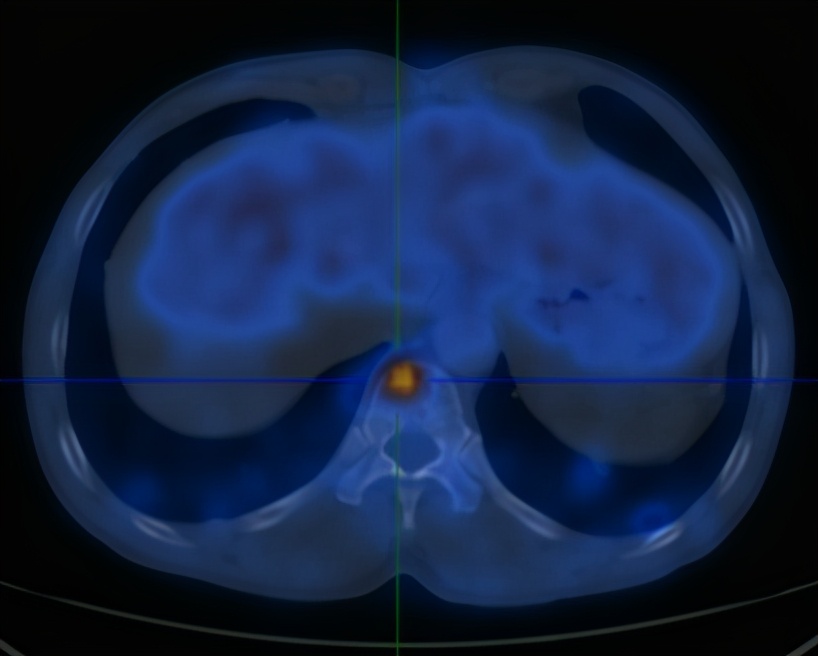

2020-6-19患者行全身PET/CT示:

1、左下肺前内基底段支气管开口处结节,糖代谢增高,考虑中央型肺癌并远端阻塞性炎症、不张;全身(双侧颈部、双侧锁骨上下窝、两侧肺门、纵隔、贲门旁、胰头后方、腹主动脉旁及双侧髂血管旁)多发淋巴结转移;双肺多发转移;肝S4及S5转移;胰头部结节转移;全身多发骨转移;综上,建议活检除外结核。